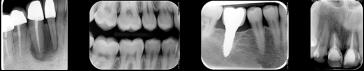

La technologie de pointe de la septième génération La détection optimale des détails à une dose de rayonnement des plus faibles est absolument convaincante. La représentation des niveaux de gris les plus fins permet de détecter les lésions cariées D1 de manière sûre. Grâce à la disponibilité rapide des images et la précision élevée des détails (par ex. représentation des limes ISO 06), VistaRay 7 constitue un complément précieux à la technologie des écrans à mémoire dans le domaine de l'endodontie ou du contrôle des piliers prothétiques .

VistaRay 7

capteur radiographique intra-oral HD direct USB

Le capteur intraoral haute résolution, Fiable et Robuste